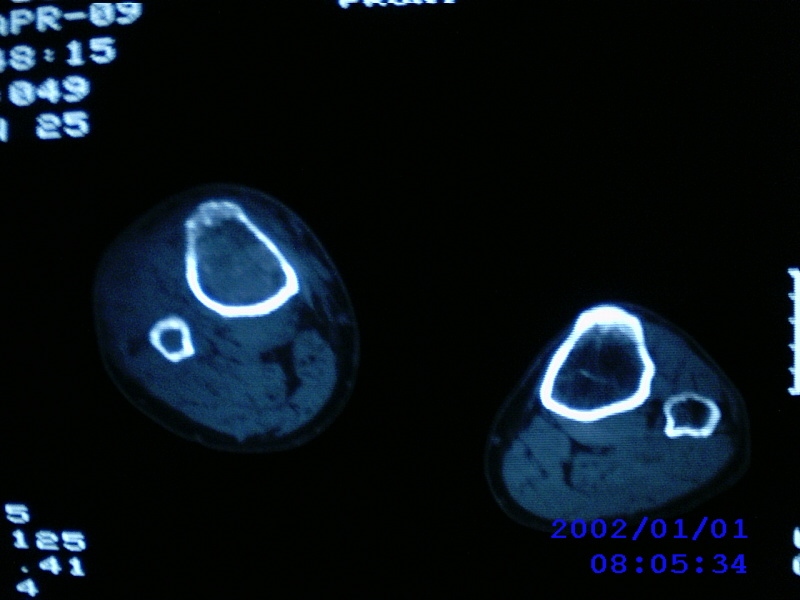

患者,男性,57岁,右侧膝关节疼痛伴肿脹10余年,加重一个月。

关节积液,关节间隙变窄,边缘骨破坏。考虑膝关节tb

关节积液,关节间隙变窄,骨质疏松,多发骨破坏,边缘轻度硬化,近端胫腓骨髓腔软组织充填,患者病史较长,支持考虑结核

有皮质的破坏~有死骨存在

多发骨破坏,骨质疏松,关节积液。考虑右膝关节结核。